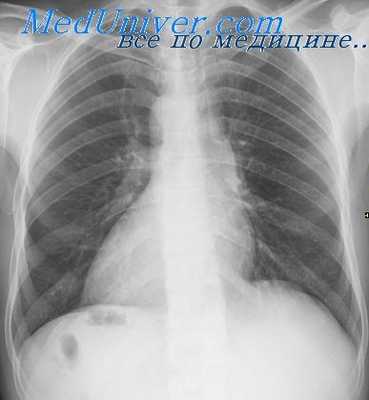

При опросе больных или их родственников необходимо установить время появления изменепий со стороны сердца для того, чтобы составить представлепие о врожденном или о приобретенном их характере. Иногда сами больные по сердцебиению, ощущаемому при физической нагрузке в правой половине грудной клетки, могут предполагать наличие у них праворасположенного сердца.

При осмотре больного обращают внимание на цвет кожных покровов и видимых слизистых оболочек. О праворасположенном сердце может свидетельствовать пальпация верхушечного и сердечного толчка справа от грудины. У больных с сопутствующими врождепными пороками сердца дополнительно к указанным признакам в этой же области можно видеть «сердечный горб» и пальпировать систолическое дрожание, а при аускультации определять максимум сердечных шумов.

С помощью перкуссии сердца определяются границы относительной и абсолютной сердечной тупости. Однако этому методу в настоящее время придают второстепенное значение в результате применения более точных методов исследования сердца, к которым следует отнести рентгенологический и рентгеноконтрастный методы.